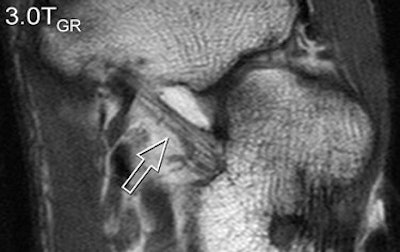

| A 31-year-old healthy male volunteer. Axial T1-weighted fast spin-echo images of foot show superior delineation of spring ligament (arrow) at 3 T (top and middle) as opposed to 1.5 T (below); 3.0TGR = 3.0T with GRAPPA algorithm. No significant difference was found between (top) and parallel (middle) acquisitions at 3 T; visualization of this ligament was rated very good at 3 T and as moderate at 1.5 T (below) by both radiologists. |

According to the results, GRAPPA MR resulted in a 44% reduction in scan time compared with conventional imaging. SNRs and CNRs doubled on the SPGR sequence at 3 tesla. These 3-tesla images also demonstrated comparable edge sharpness.

Image quality was rated highest on 3-tesla images. The axial T1-weighted sequence was given an average score of 3.4 at 3 tesla for parallel and normal acquisitions versus a score of 2.8 for 1.5 tesla. Visualization of ligaments and tendon abnormalities were also rated highly on parallel 3-tesla MR.